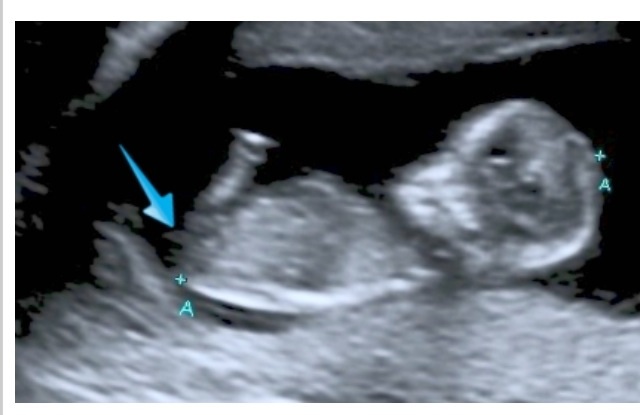

12+1 wk nub and potty shots. Pleeeeease let me know what you think. And zoom in on nub and let me know your thoughts. Thanks x

No nub visible in the profile shot & potty shots are almost never distinguishing this early, but if forced to guess...maaaaaaaaybe girl?

Can u see nub now maidentomother?Attachment 22685

I don't think that's the nub

Nothing clear to guess on the nub is very distorted and mostly cut off. You have a girly skull though